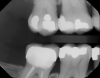

Fig 10. Decay evident, teeth J and K, on x-ray of caries-prone 6-year-old patient.

Figure 10

Fig 11. Transillumination image confirmed caries.

Figure 11

In another case of a caries-prone 6-year-old patient, the clinician, who generally avoids taking x-rays on children, opted to take them this time because lesions can grow rapidly.13 The transillumination caries detector also was used to attain a more complete diagnosis and to find problems as early as possible. Decay appeared on both the x-ray (Figure 10) and the CariVu image (Figure 11). Viewing the situation from multiple perspectives enables treatment to be as conservative as possible because the clinician can pinpoint exactly where the decay is present on the tooth.